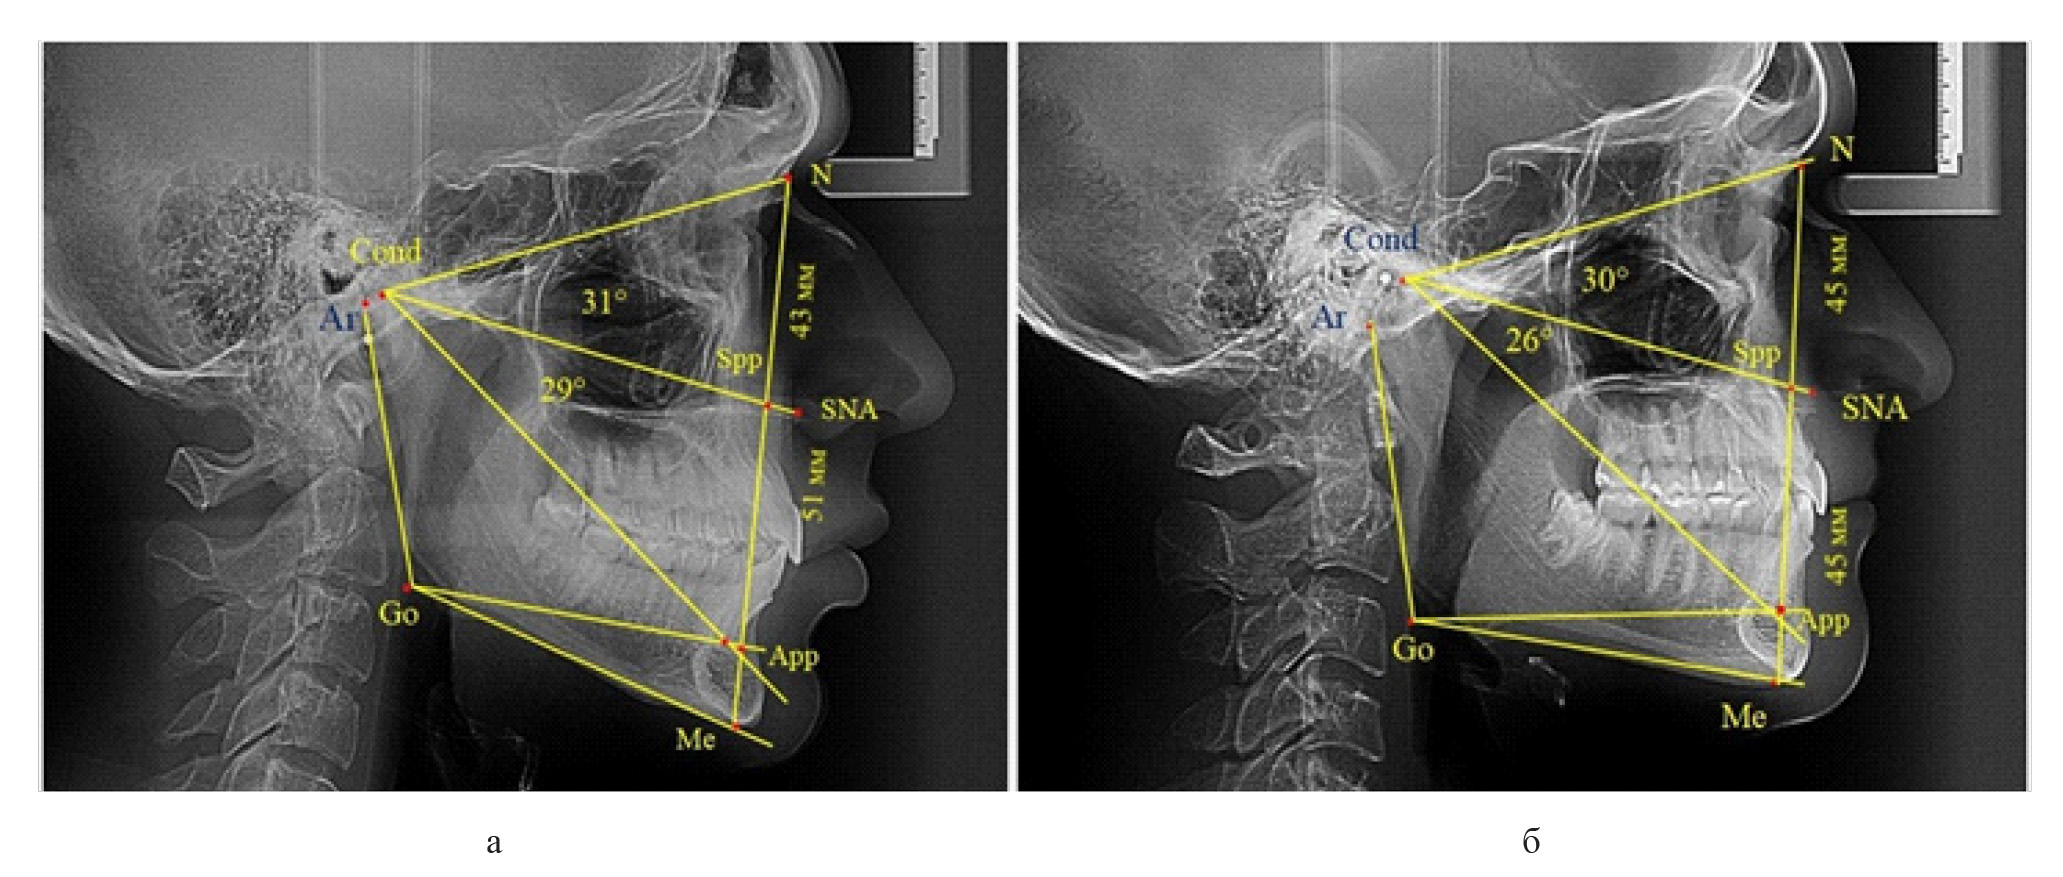

Признаки снижения высоты назального отдела вплоть до уровня горизонтального патологического типа при физиологической окклюзии были определены у 10 человек [(17,86 ± 5,11) %]. При этом параметры гнатического отдела соответствовали физиологической норме либо физиологическому горизонтальному типу (рис. 4).

Рис. 4. Варианты ТРГ с укороченными размерами носового отдела и оптимальными (а) и укороченными (б) размерами гнатической части

Среди пациентов с аномалиями челюстно-лицевой области в вертикальном направлении у 24 человек определялась глубокая резцовая окклюзия/дизокклюзия (рис. 5).

Рис. 5. Варианты ТРГ с оптимальными размерами носового отдела и оптимальными (а) и укороченными (б) размерами гнатической части лица

При этом только в двух случаях [(8,33 ± 5,64) %], параметры носового и гнатического отдела соответствовали норме. У 9 человек [(37,59 ± 9,88) %], при оптимальных параметрах назального отдела отмечалось уменьшение высоты гнатического отдела, вплоть до патологических показателей.

У людей с глубокой резцовой окклюзией нередко отмечалось изменение параметров носового отдела лица. Так, в 7 случаях было выявлено снижение параметров как носового, так и гнатического отделов лица. У 5 человек [(20,83 ± 8,28) %], отмечалось уменьшение носового отдела лица при оптимальных параметрах гнатического отдела.

В одном случае [(4,17 ± 4,08) %], определялось патологическое увеличение назального отдела лица при уменьшении гнатической его части. Некоторые варианты ТРГ пациентов с глубокой резцовой окклюзией представлены на рис. 6.

Рис. 6. Варианты ТРГ с уменьшенными размерами носового отдела и оптимальными (а) и укороченными (б) размерами гнатической части лица при глубокой резцовой окклюзии